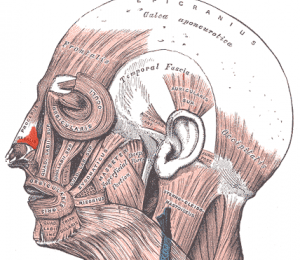

Levator labii superioris alaeque nasi

De levator labii superioris alaeque nasi is een dunne, ...

Levator labii superioris

De levator labii superioris is een dunne vierhoekige sp...

Levator labii inferioris

De levator labii inferioris ontspringt aan de voorzijde...